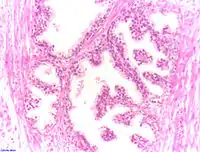

Adénocarcinome prostatique

Adénocarcinome ; tissus indifférenciés

Invasion périneurale par un adénocarcinome prostatique. HE, x400